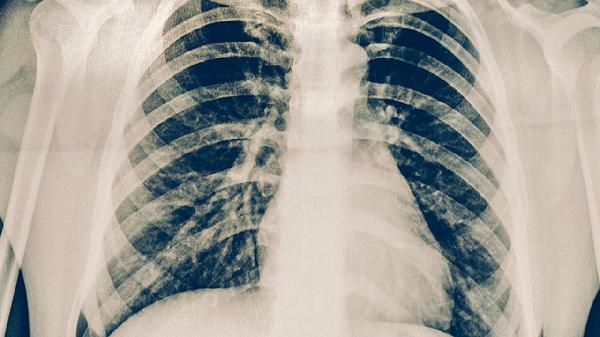

胸膜受累的耐药肺结核患者会出现针刺样胸痛,深呼吸或咳嗽时加重。胸痛与胸膜炎症、粘连或包裹性积液有关,普通镇痛药如布洛芬缓释胶囊难以缓解。胸部X线可能显示胸膜增厚或钙化,需通过胸腔积液检查排除合并感染。治疗上需加用左氧氟沙星片等氟喹诺酮类药物。